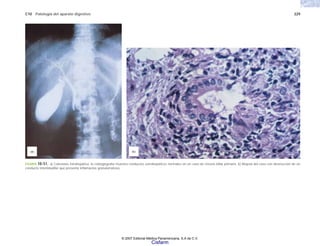

FIGURA 2-3. Aspecto radiológico del esqueleto de un niño recién nacido con

osteogénesis imperfecta grave (tipo I). (Cortesía de la Dra. Sandra Carnevale.)